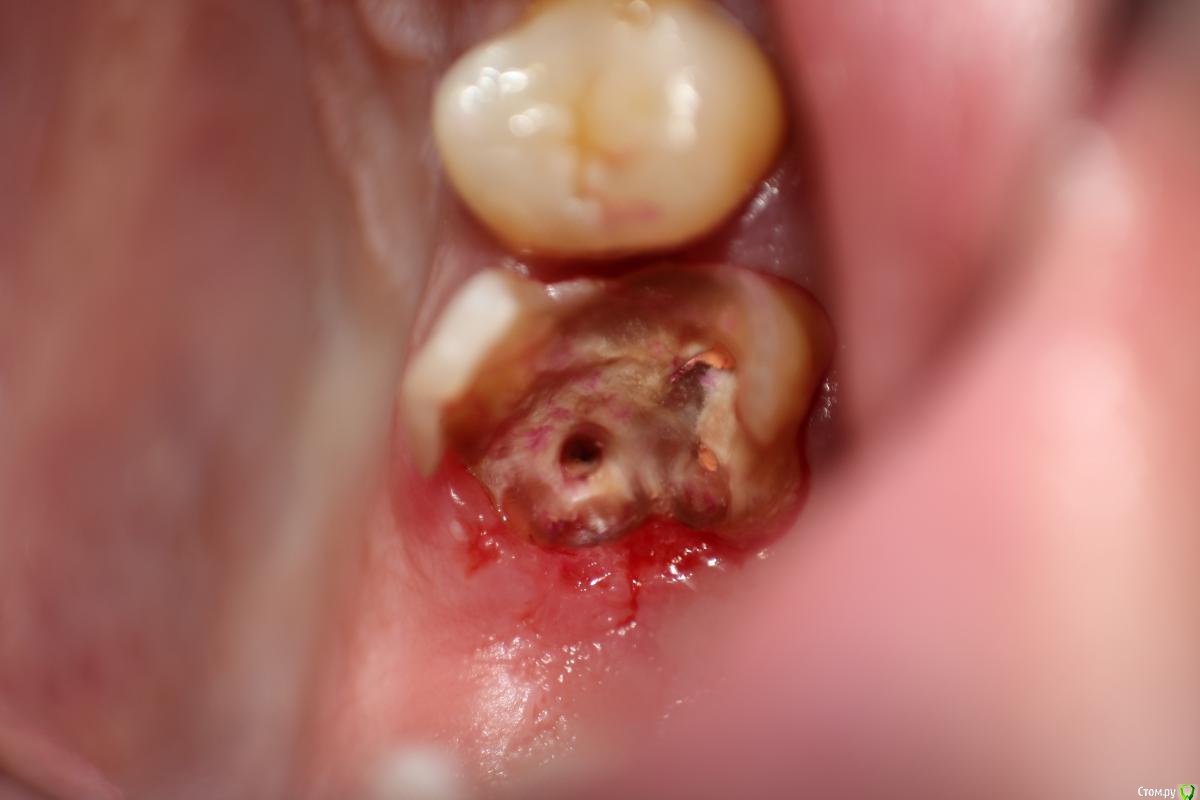

Витторио Орлионе Опубликовано 17 января, 2017 Поделиться Опубликовано 17 января, 2017 (изменено) а что скажете про такой случай?! Быть удалению или не быть?!? Изменено 17 января, 2017 пользователем Витторио Орлионе Ссылка на комментарий

krokomot Опубликовано 17 января, 2017 Поделиться Опубликовано 17 января, 2017 а что скажете про такой случай?! Быть удалению или не быть?!?удаление, фуркация поражена Ссылка на комментарий

chervoncevdaniil Опубликовано 17 января, 2017 Поделиться Опубликовано 17 января, 2017 Удалять Ссылка на комментарий

Витторио Орлионе Опубликовано 17 января, 2017 Поделиться Опубликовано 17 января, 2017 (изменено) Вот он Изменено 17 января, 2017 пользователем Витторио Орлионе Ссылка на комментарий